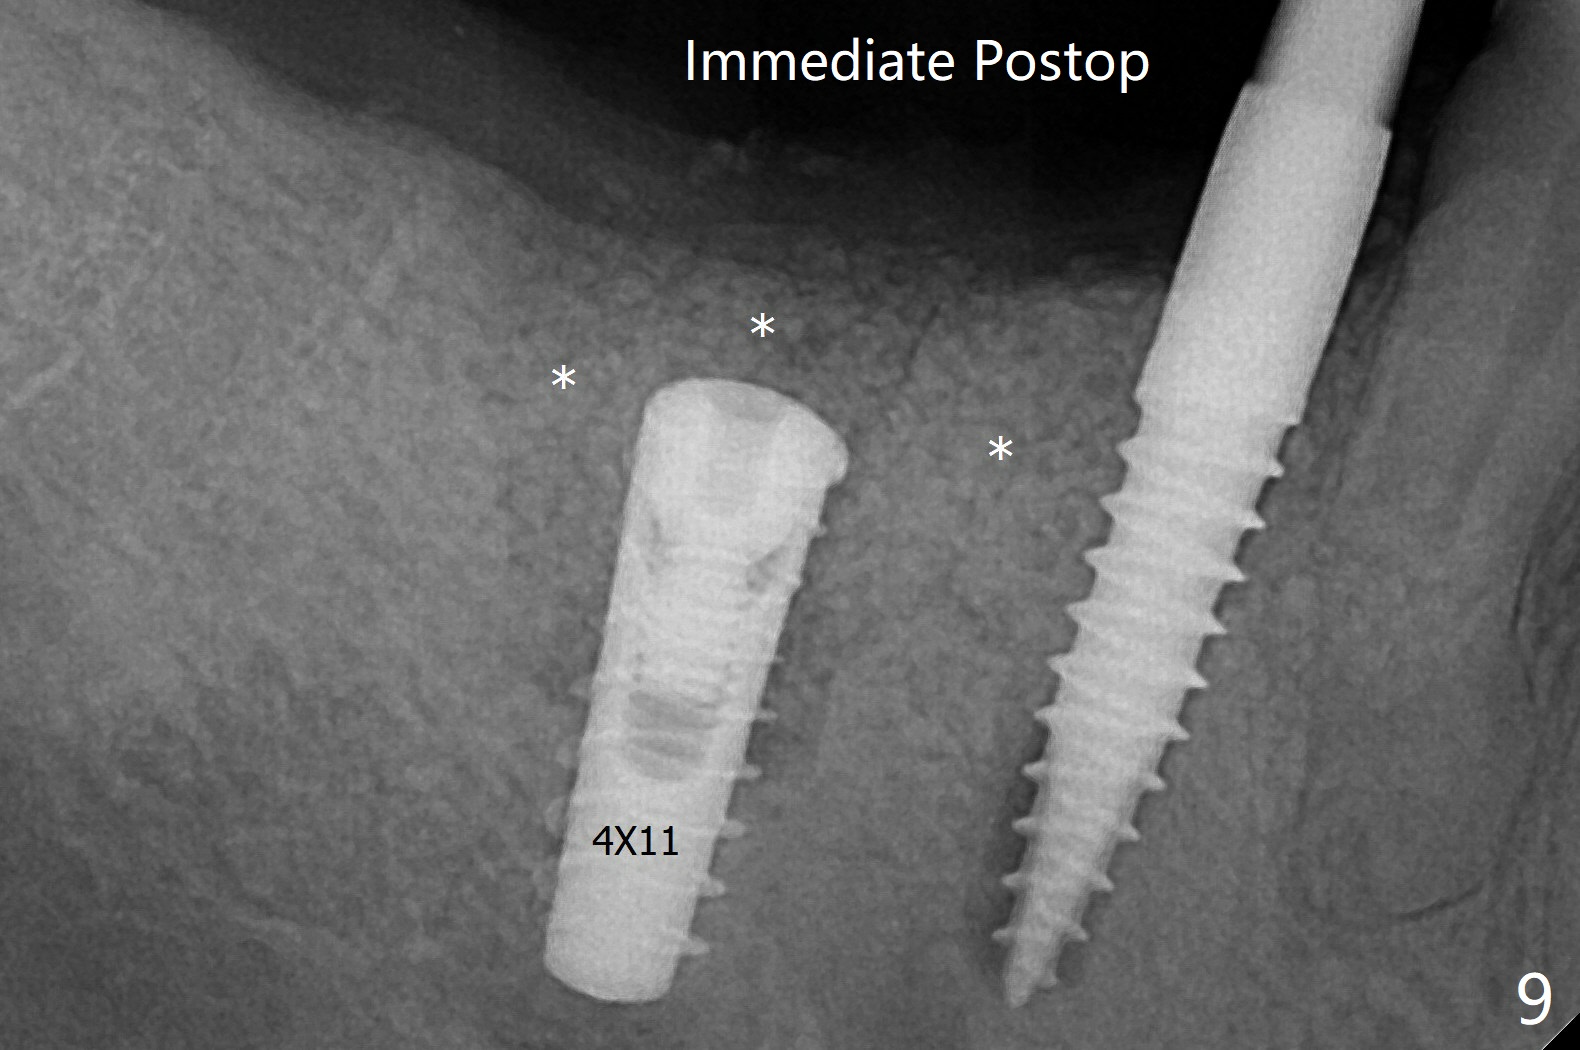

Since primary stability is lower (<20 Ncm vs. 35 Ncm associated with the implant #29), an abutment is not placed, which may be favorable to healing, but it is difficult to achieve primary closure. After bone graft (Fig.9 *) and 2 layers of PRF, Cytoplast is placed. While the bone height decreases at #29, the bone density at #30 increases 4.5 months postop (Fig.15). The gingiva heals.